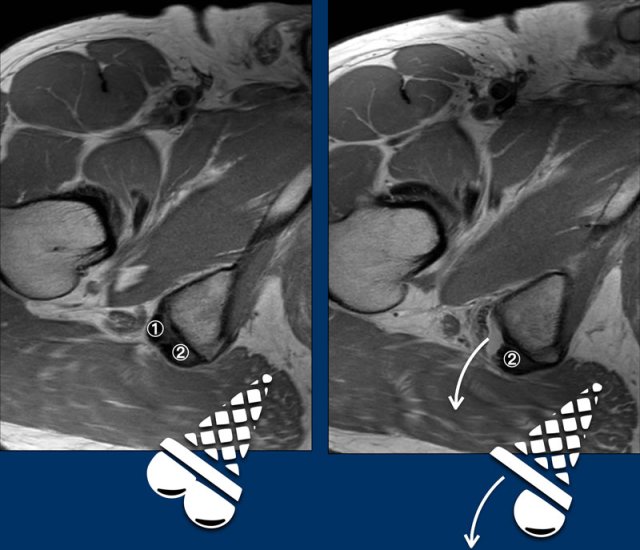

Dropped icecream sign

It is best to determine which tendon is torn on axial images.

The ischial tuberosity can be regarded as an icecream cone with the tendon of the semimembranosus (anterolateral ) and the conjoint tendon (posteromedial ) as two scoops with the flavor StracciatelLa CaraMel.

The image shows an avulsion of the semimembranosus tendon.

① tendon of the semimembranosus

② conjoint tendon

Remember the flavours:

Stracciatella - Semimembranosus lateral

Caramel - Conjoint medial

In this patient both the right semimembranosus tendon aswell as the conjoint tendon are avulsed.

Both scoops have dropped.